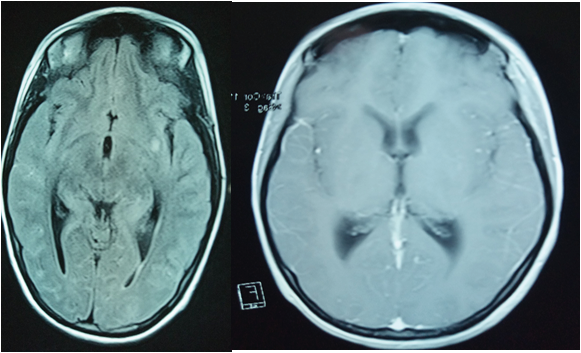

Seventeen year old patient with no previous history consulted in the emergency room for febrile meningeal syndrome complicated by disturbance of consciousness with acute settling paraplegia with acute urine retention. On admission, she was found to be a drowsy, hemodynamically stable patient with arterial pressure 127/65 mmgh, heart rate 100bpm, eupneic 20 c/min and saturation 99%, febrile at 39 degrees. Neurological examination revealed a flaccid paraplegia rated at 0/5 with an umbilical sensory level, abolished ROTs, left convergent strabismus, and a bladder globe. The rest of the physical examination was unremarkable. An emergency brain CT scan did not reveal any abnormality and a lumbar puncture revealed a xanthochromic aspect, hyperproteinorachia: 2. 98 g/l hypoglycorachia: 0.05 g/l (glycemia: 1.05) With cellulorachia at 40 with lymphocyte predominance in 60%. Treatment based on C3G meningeal dose, acyclovir at a rate of 10 mg/kg/8h and anti-TB quadritherapy (protocol) was started. Emergency spinal cord MRI to eliminate spinal cord compression, in order to objectify transverse myelitis extending over the entire lumbar region and polyradiculoneuritis involving the roots of the ponytail (figure 1).

Figure 1: Medullary MRI (Transverse Myelitis Extending Over the Entire Lumbar Region and Polyradiculoneuritis Involving the Roots of the Ponytail)

In our case it is a transverse myelitis extending over the entire lumbar region and a polyradiculoneuritis involving the roots of the horse tail (figure 1).